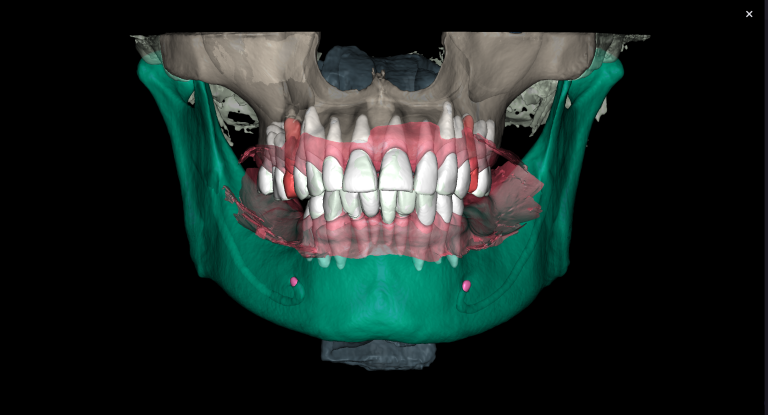

Solution: The automated process of segmentation and formation of 3D models from DICOM files allows extracting individual structures for subsequent 3D printing. The printed model of the third molar, taken from the “STL” module of Diagnocat, is used to prepare the socket for the transplanted tooth. The 3D reconstruction generated using Diagnocat displays the structure of the jaws and teeth and enables the visualization of tooth 37 (Universal 18) with periapical lesion around the roots. In this case, Diagnocat serves as a communication tool that helps convince the patient of the importance of timely implementation of the proposed treatment plan.